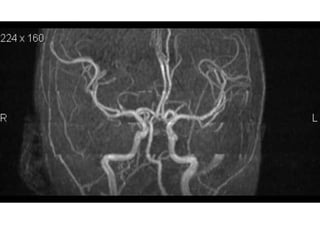

NORMAL MRA

Arteries of the brain (cranial view) - MRA

1. Anterior cerebral artery

2. Anterior communicating artery

3. Basilar artery

4. branches (in insula) of middle

cerebral artery

5. Cavernous portion of internal carotid

artery

6. Cervical portion of internal carotid

7. Genu of middle cerebral artery

8. Intracranial (supraclinoid) internal

carotid artery

9. Middle cerebral artery

10. Ophthalmic artery

11. Petrous portion of internal carotid

12. Posterior cerebral artery

13. Posterior cerebral artery in ambient

cistern

14. posterior cerebral artery in

interpeduncular cistern

15. Posterior communicating artery

16. Posterior inf cerebellar artery.

17. Quadrigeminal portion of posterior

18. Superior cerebellar artery

19. Vertebral artery